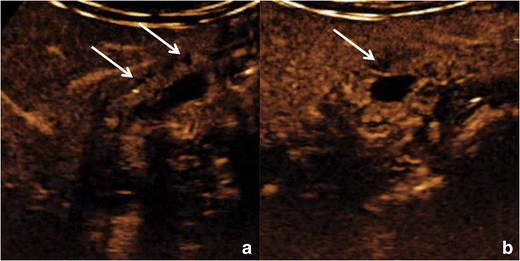

Imaging findings

The thickened gallbladder wall shows the same degree of enhancement as the adjacent normal wall in the majority of the cases, whereas a relative hyper-enhancement may be observed in about 15% of the cases. Wall enhancement typically shows a trilaminar pattern during the arterial phase as a consequence of increased mucosal and serosal vascularization. The external layer must show no discontinuities.

Avascular spaces, representing RAS, must be observed within the thickened gallbladder wall (Fig. 9). RAS appear avascular in every phase of the dynamic study, independently from their content. The identification of avascular spaces within a gallbladder wall thickening is virtually pathognomonic for GA.

Fig. 9

Gallbladder adenomyomatosis: typical contrast-enhanced ultrasound (CEUS) findings. On CEUS, the thickened gallbladder wall shows discrete contrast enhancement, whereas Rokitansky–Aschoff sinuses (arrows) appear as avascular structures during every phase of the exam

Bild vergrößern